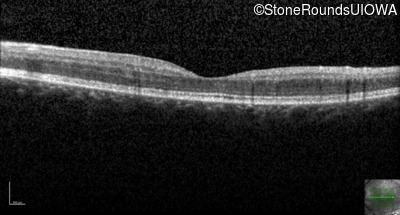

Age at visit: 18 years